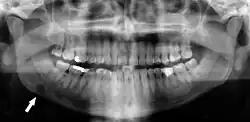

Dental panoramic radiograph showing Stafne defect in the right mandible, below the inferior alveolar nerve canal (arrowed, appears on lower left of image). This x-ray was taken for an unrelated assessment of wisdom teeth, and the Stafne defect was a chance finding.

Stafne's defect is usually discovered by chance during routine dental radiography.[11] Radiographically, it is a well-circumscribed, monolocular, round, radiolucent defect, 1–3 cm in size, usually between the inferior alveolar nerve (IAN) and the inferior border of the posterior mandible between the molars and the angle of the jaw. It is one of the few radiolucent lesions that can occur below the IAN. The border is well corticated and it will have no effect on the surrounding structures. Computed tomography (CT) will show a shallow defect through the medial cortex of the mandible with a corticated rim and no soft tissue abnormalities, with the exception of a portion of the submandibular gland. Neoplasms, such as metastatic squamous cell carcinoma to the submandibular lymph nodes or a salivary gland tumour, could create a similar appearance but rarely have such well defined borders and can usually be palpated in the floor of the mouth or submandibular triangle of the neck as a hard mass. CT and clinical exam is typically sufficient to distinguish between this and a Stafne defect. The Stafne defect also tends to not increase in size or change in radiographic appearance over time (hence the term "static bone cyst"), and this can be used to help confirm the diagnosis.[11] Tissue biopsy is not usually indicated, but if carried out, the histopathologic appearance is usually normal salivary gland tissue. Sometimes attempted biopsy of Stafne defects reveals an empty cavity (possibly because the gland was displaced at the time of biopsy), or other contents such as blood vessels, fat, lymphoid or connective tissues. Defects of the anterior lingual mandible may require biopsy for correct diagnosis at this unusual location.[5] The radiolucent defect here may be superimposed on the lower anterior teeth and be mistaken for an odontogenic lesion. Sometimes the defect may interrupt the contour of the lower border of the mandible, and may be palpable. Sialography may be sometimes used to help demonstrate the salivary gland tissue within the bone.